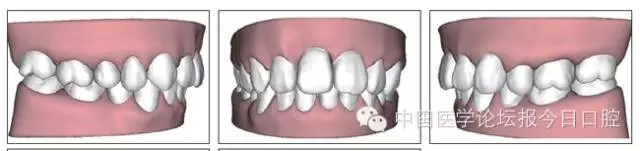

患者共戴用矯治器上頜32步,下頜26步。

矯治后,牙列間隙關閉,面型及覆(牙合)覆蓋改善。11根尖片(圖8)顯示,治療后較治療前,牙周支持組織增加,牙槽骨角形吸收區(qū)水平向縮小0.3mm,垂直向縮小0.6mm。11松動Ⅰ度,余切牙無松動。

矯治結果及臨床總結

圖11 治療后ODS模型